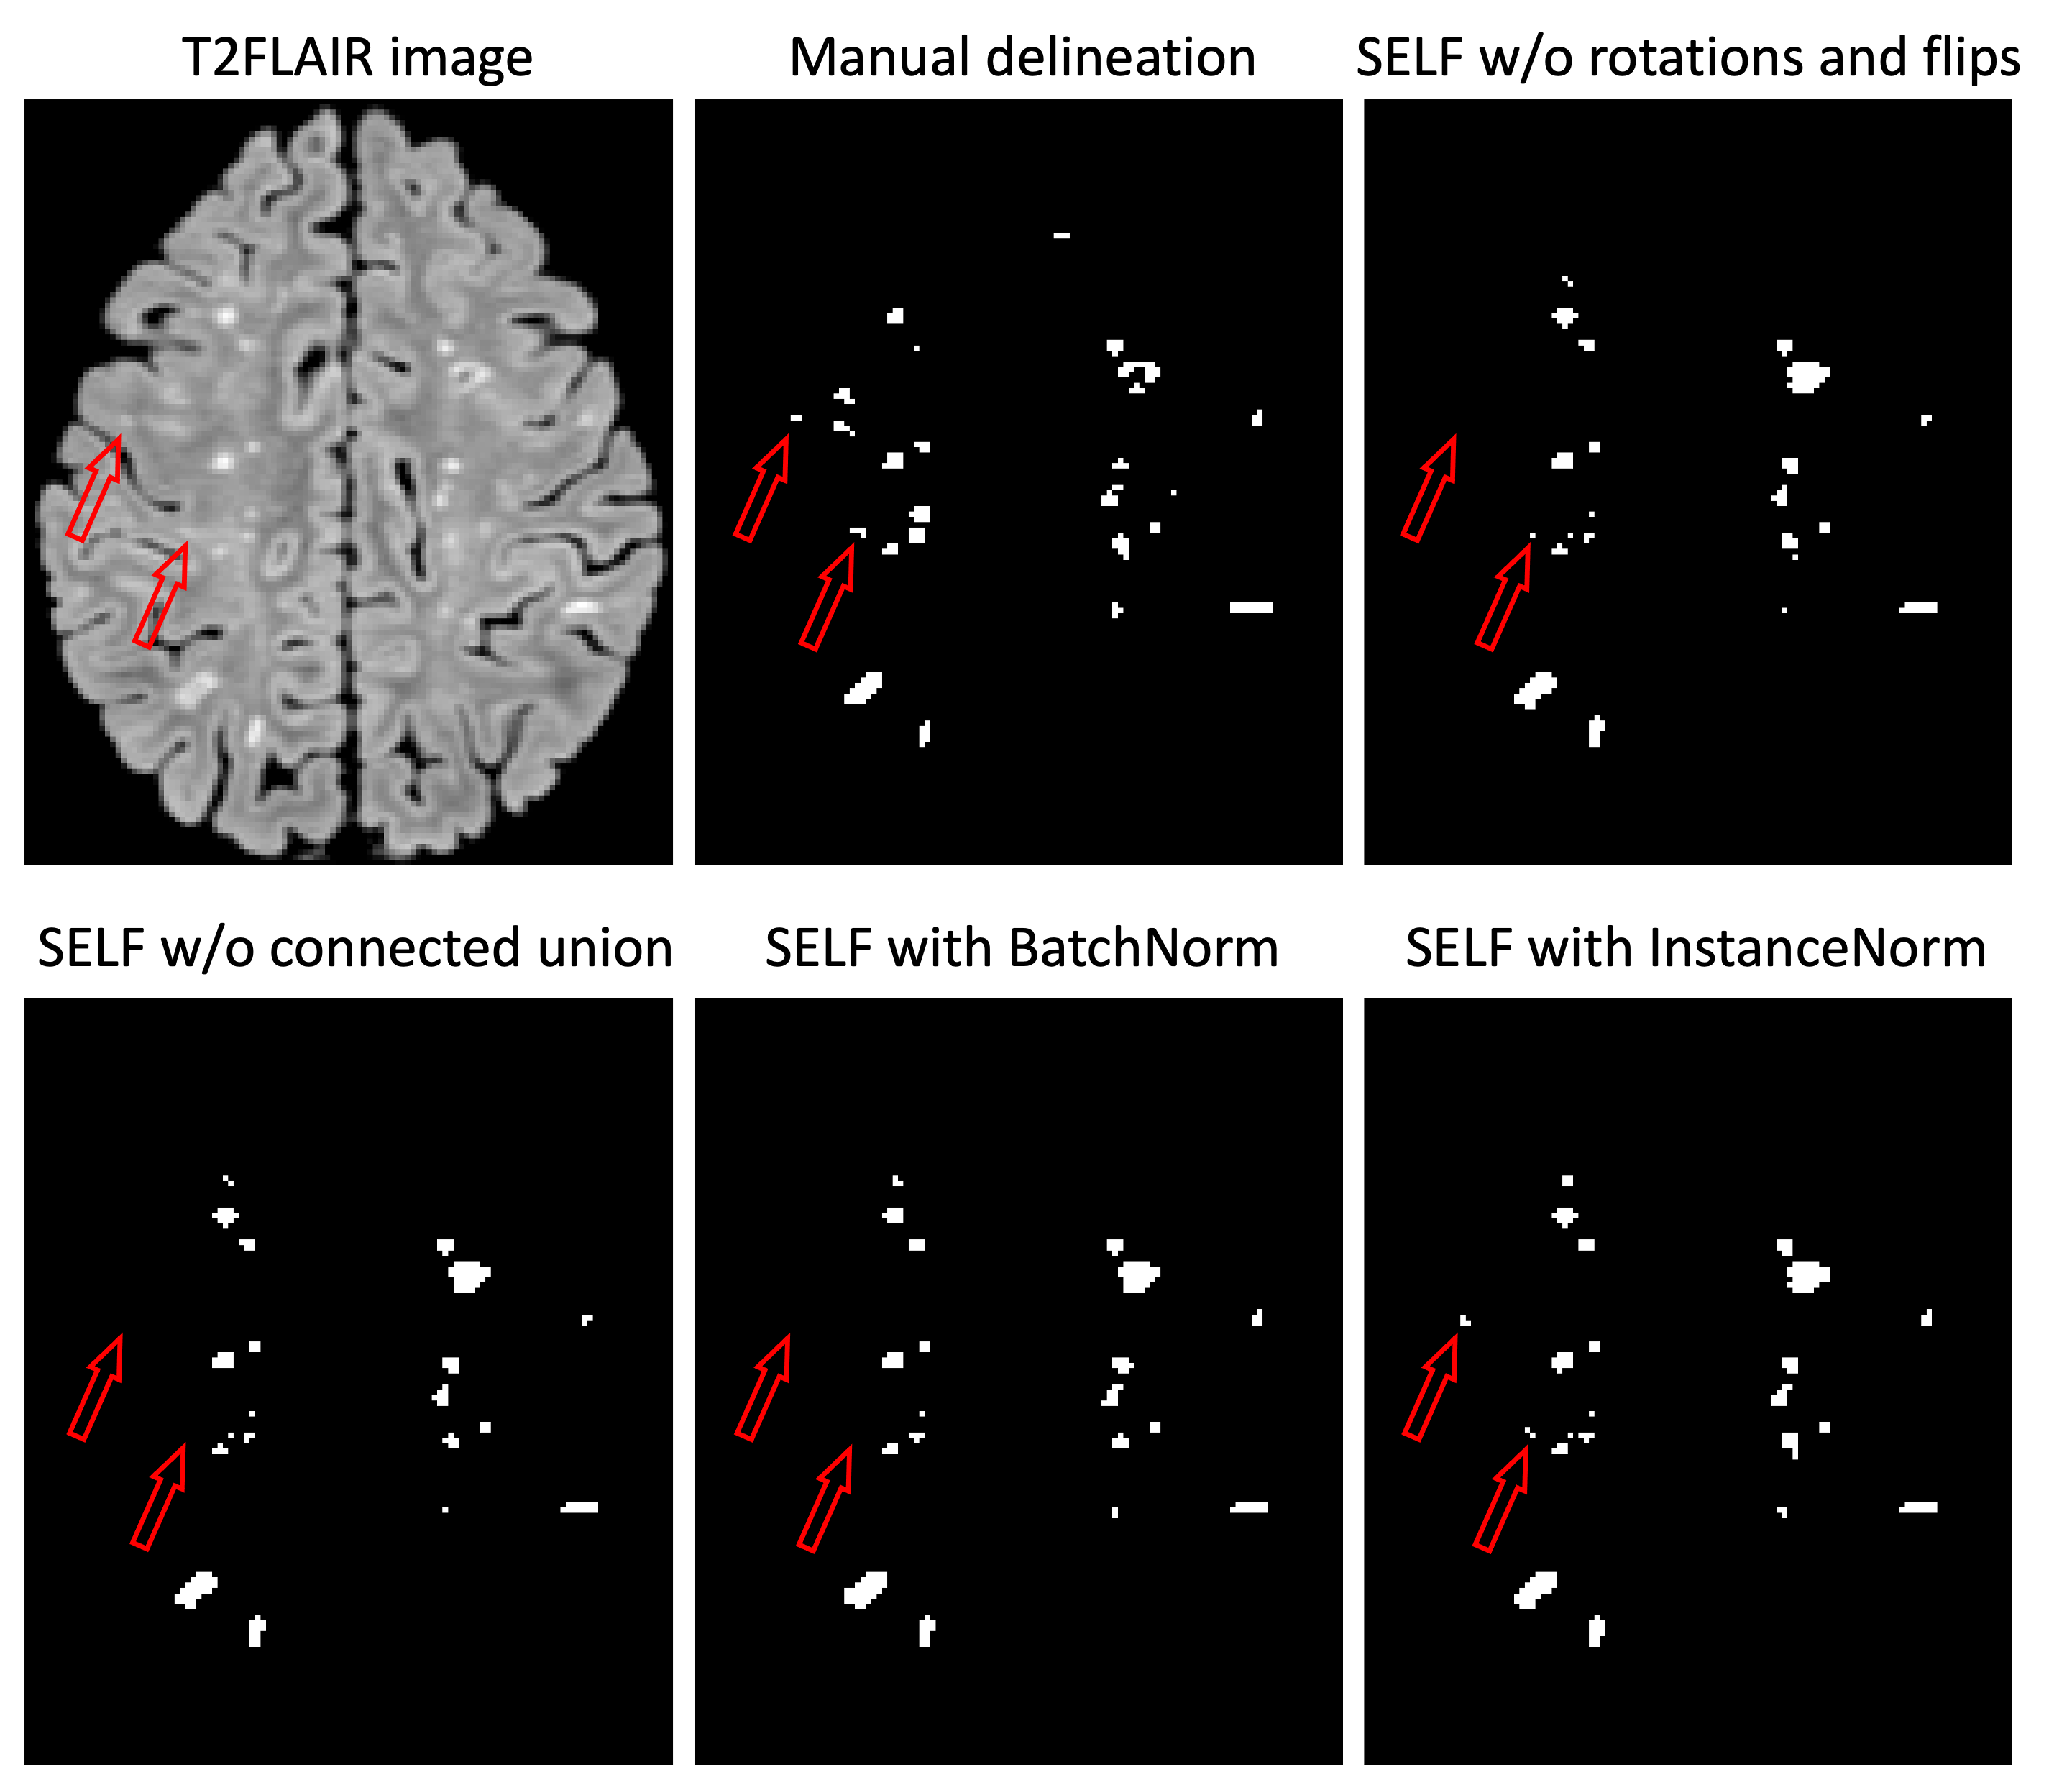

Refer to caption

Fig. 3: Segmentation results of ISBI trained model on one out-of-domain test subject with manual delineation reference.

3.3 Out-of-domain Test Dataset with Labels

We tested the generalization of SELF trained on ISBI using one out-of-domain dataset, which consists of 10 patients with manual delineation of MS lesions by an experienced radiologist. Similar to the ISBI ablation study, we compared to three orientation inputs without rotations and flips (similar to Tiramisu), intersection without connected union, and batch normalization instead of instance normalization. The source code of ALL-Net is not made public and therefore not compared here. Table 3 shows the performance metrics, presenting consistent improvement and accurate segmentation as in Table 2. Fig. 3 shows a representative test subject with multiple small lesions. With manual delineation as a reference, more lesions (highlighted by red hollow arrows) were captured by SELF with instance normalization.